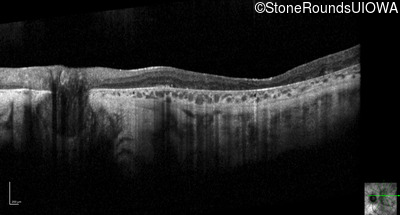

Optical Coherence Tomography - Right - 10/100 -2

Exemplar / OCT Stack